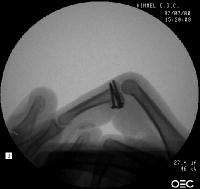

Xrays show a comminuted dorsal fracture dislocation of the proximal interphalangeal joint with dorsal subluxation.

The joint moves, but through an unnatural hinging on the edge of the fracture.